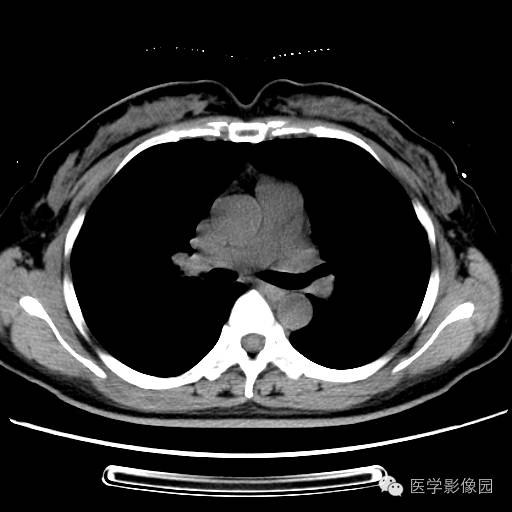

肺叶实变性支气管肺泡癌1例CT影像表现

【病例】肺叶实变性支气管肺泡癌1例CT影像表现